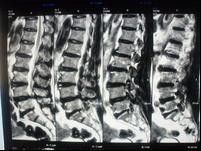

X線片上沒有椎間隙狹窄等明顯的退行性改變,但可以有腰椎生理曲線的改變,椎體間不穩定及輕度骨質增生等變化。此型在臨床上極為常見,是最早期的腰椎病。由於症狀較輕,往往重視不夠,以致反覆發作使病情加重。從大量的臨床觀察證實,此型實際上是腰椎病的最初階段,也是治療最為有利的時機。